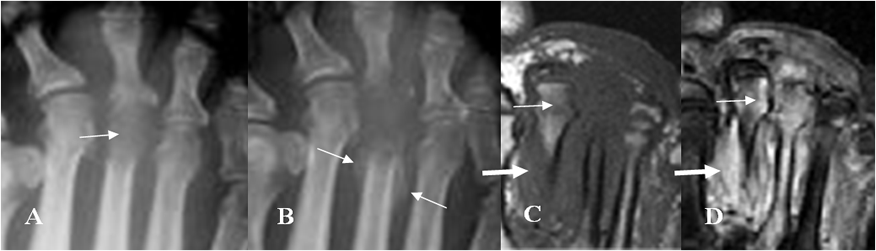

Fig 64 C. Artritis séptica.

A: Rx AP. Lesión lítica en la parte distal del 3º metatarsiano, por osteomielitis.

B: Rx AP. Progresión de la destrucción ósea. Adicionalmente se identifica reacción perióstica asociada. (Flechas).

C: RM axial en T1 y B: RM axial en STIR. 3º metatarsiano hipointenso en T1 e hiperintenso en STIR, con destrucción de su cabeza, por osteomielitis. Hay extensión por contigüidad de los cambios inflamatorios a la cabeza del 2º metatarsiano (Flechas delgadas) y edema en los tejidos blandos adyacentes. (Flechas gruesas).